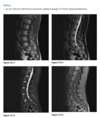

An anteroposterior view of the pelvis

(Fig. 2.24.1) in an elderly man shows extensive thick-

ening of the right iliopectineal line (arrows) with

coarsening of the trabecular pattern and increased

sclerosis throughout the entire right hemipelvis.

Paget disease (i.e., osteitis deformans)

disordered bone

remodeling affecting osteoblastic and osteoclastic

activity. Osseous involvement may be monostotic

or polyostotic, and 80% of the patients are asymp-

tomatic at the time of the discovery of the disease,

usually as an incidental finding on radiography or

because of elevated serum alkaline phosphatase and

elevated serum and urinary hydroxyproline.

stage I (acute phase), active and unbalanced osteo-

clastic bone resorption usually causes areas of lytic

bone destruction. In stage II (intermediate phase),

increased osteoblastic activity results in thickening of the cortex, coarsening of the trabecular pattern,

generalized bone overgrowth, and loss of corticome-

dullary differentiation. In stage III (late or inactive

phase), there is a diffuse increase in the density of

involved bone. Stage IV is the superimposed malig-

nant degeneration of Paget disease into a osteosarcoma.

radiographic findings in the acute phase are

osteoporosis circumscripta, in which an advancing

lytic area is seen in the frontal or occipital regions of

the skull, and subarticular osteolysis in the diaphy-

ses of the tubular bones, especially the tibia, yield-

ing a flame-shaped or “blade-of-grass” appearance

(Fig. 2.24.2). In the intermediate stage, there may

be bowing of the long bones, an “ivory” or “pic-

ture frame” vertebral body (Fig. 2.24.3), and more

extensive calvarial osteosclerosis superimposed on

a background of osteolysis, resulting in the cotton-

wool appearance of the skull.

In the long bones of the lower extremity, corti-

cal thickening, increased trabecular coarseness, and

bowing can be seen (Fig. 2.24.5), and CT can confirm

these findings (Fig. 2.24.6).

MRI can be used to detect malignant sarcomatous de-

generation by showing new bone destruction, soft-

tissue masses, and bone and soft-tissue edema.